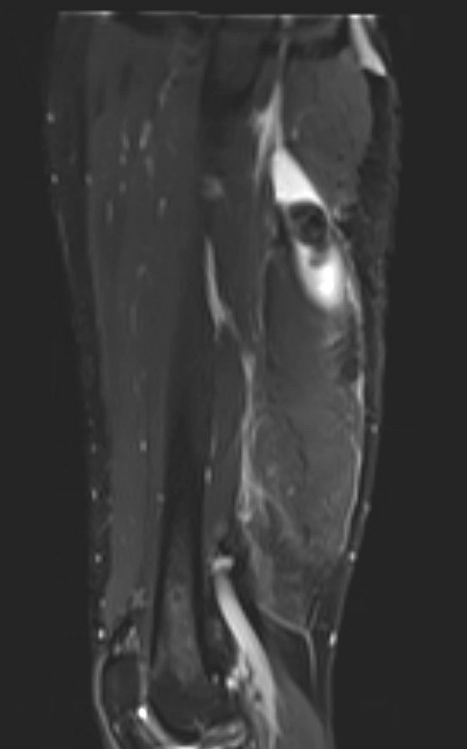

Proximal hamstring avulsion on right - red circle is retracted hamstring tendon, blue circle is normal insertion on left

Proximal hamstring avulsion, with tendon floating in hematoma / seroma